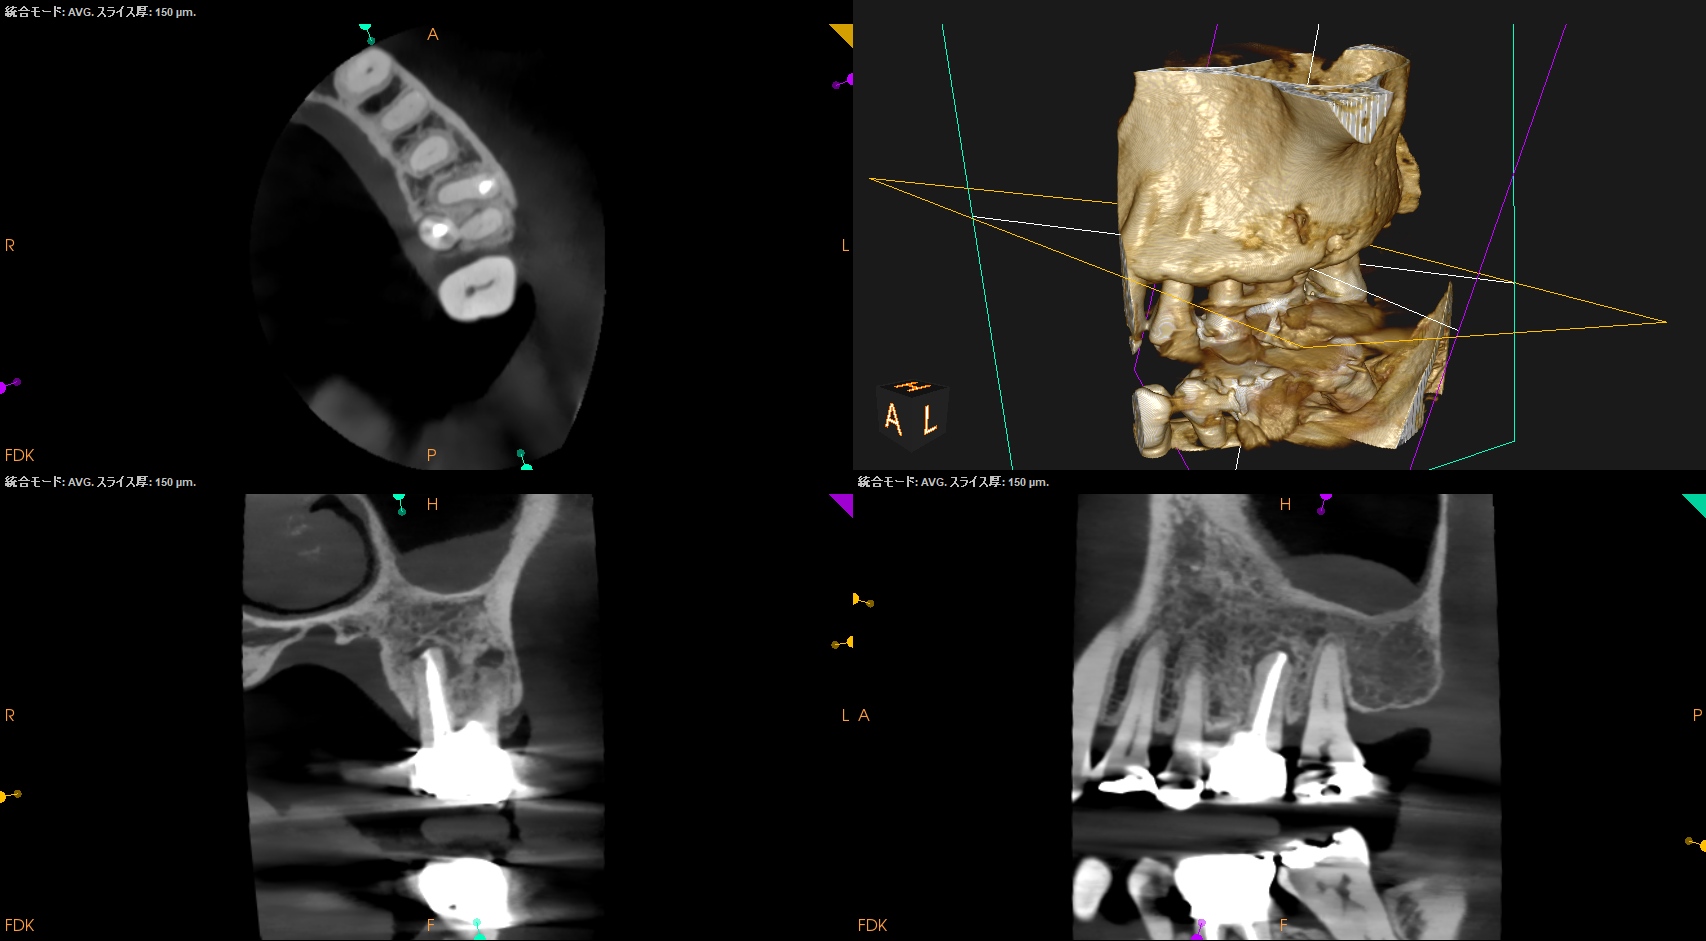

術後にPA, CBCTを撮影した。

問題はないだろう。

次回はMB,DBのApicoectomyである。